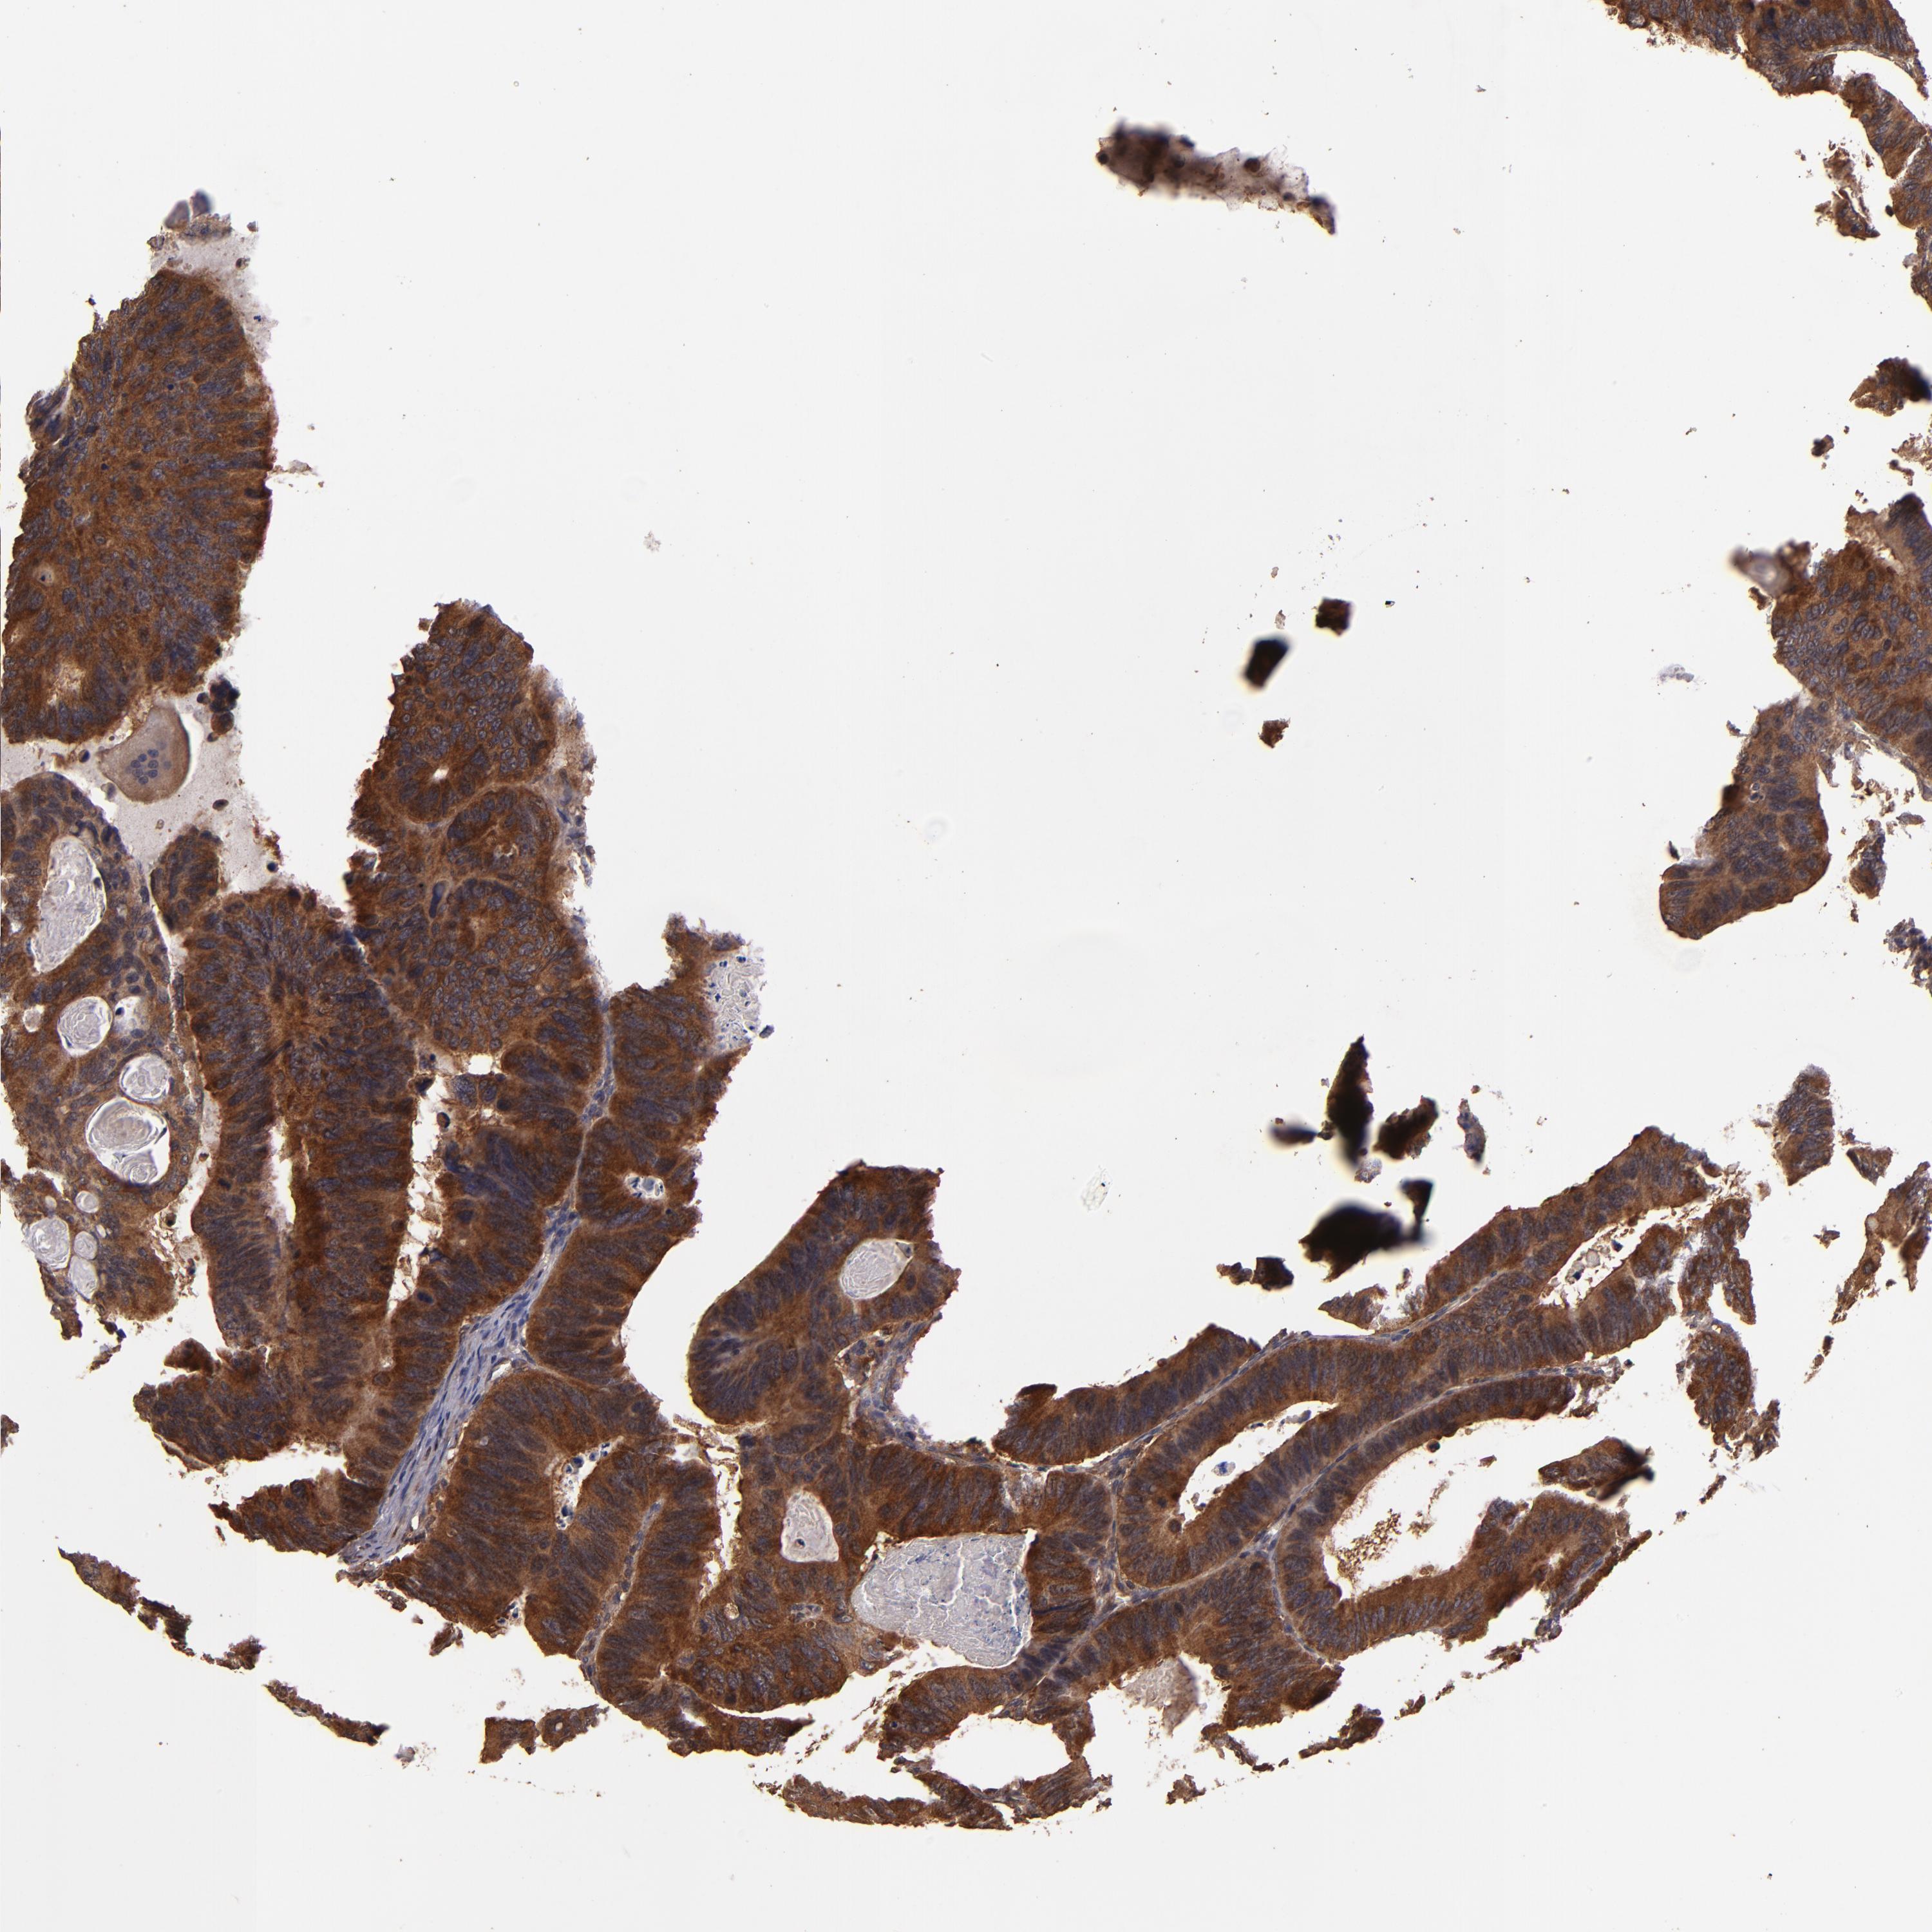

CANCER COLORECTAL CANCER Show tissue menu

Colorectal cancer

Human cancer

Colon adenocarcinoma